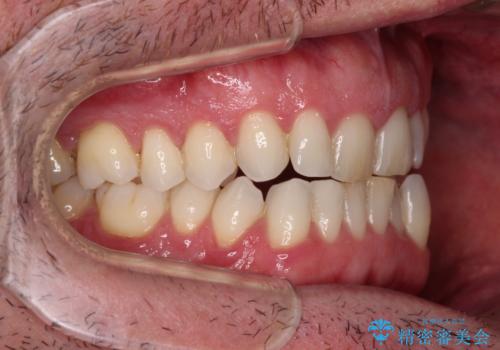

- 前歯でものを噛みきりたいとのことで来院された患者様です。

以前矯正治療を経験されたそうですが、舌の突出癖により上下前歯に隙間ができている様子でした。

舌の突出癖が改善されない限り、非接触改善は見込めないため、トレーニングを徹底するように指示しました。